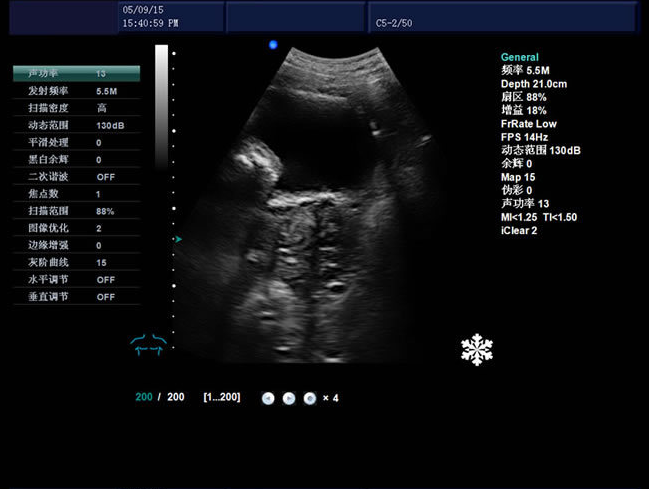

发射频率: 具有2.0MHz、3.0MHz、3.5MHz、4.0MHz、5.5MHz、5.0MHz、6.5MHz、9.0MHz、10MHZ、6.0MHz、7.5MHz、12.0MHz变频接收;

动态范围:0-160dB

分辨率:侧向≤2mm,轴向≤1mm

帧频:9-508fps